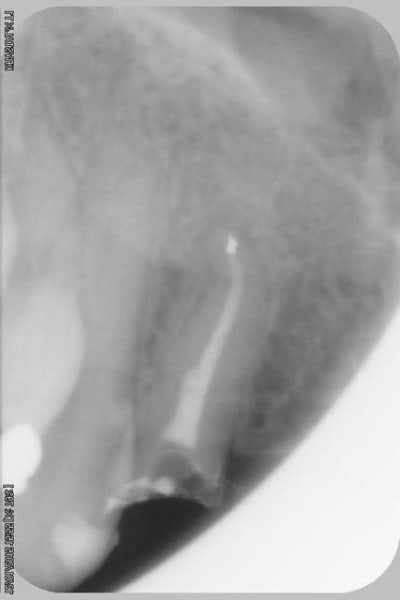

sur-traitement, pompe à fric, assassinat ...etc.. afin d'éviter tout ça je soumet à votre sagesse un cas sympa.

Patiente sympa, 30 ans, un bridge ceramo-métal fait il y a 10 ans, en fin de vie.

Les endo et les IC dans les 12-22 sont sublimes...et ça a durer 10 ans....incroyable...Il y a pas de la paro aussi ?

étonnant en effet... et encore plus étonnant, ce qui n'arrive jamais le radiologue (qui est parfaitement compétent normalement) a inversé la droite et la gauche.